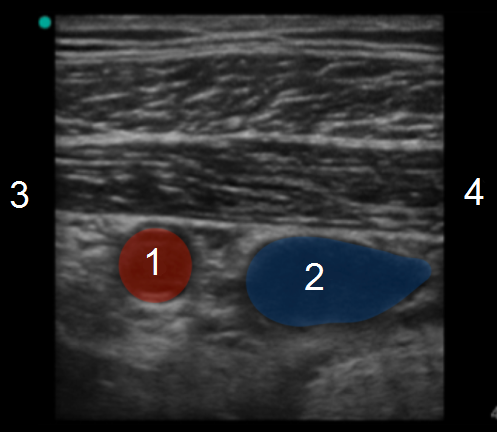

锁骨下腋动脉和静脉图像

腋动脉

腋静脉

颅内和外侧

尾侧和内侧